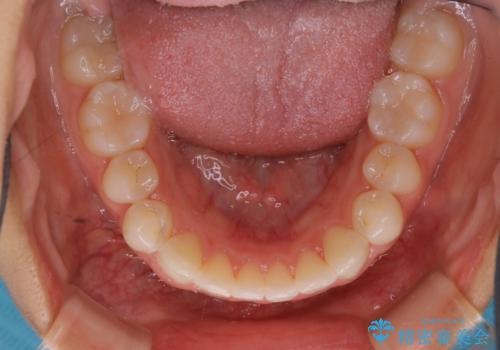

- 上下前歯のがたつきが気になるとの事で来院された患者様です。がたつきの程度が軽度であったため、インビザラインライトにて治療をおこないました。

がたつきの程度が軽度であったことと、インビザラインを正しく装着して頂けたことで短期間で治療終了することが出来ました。